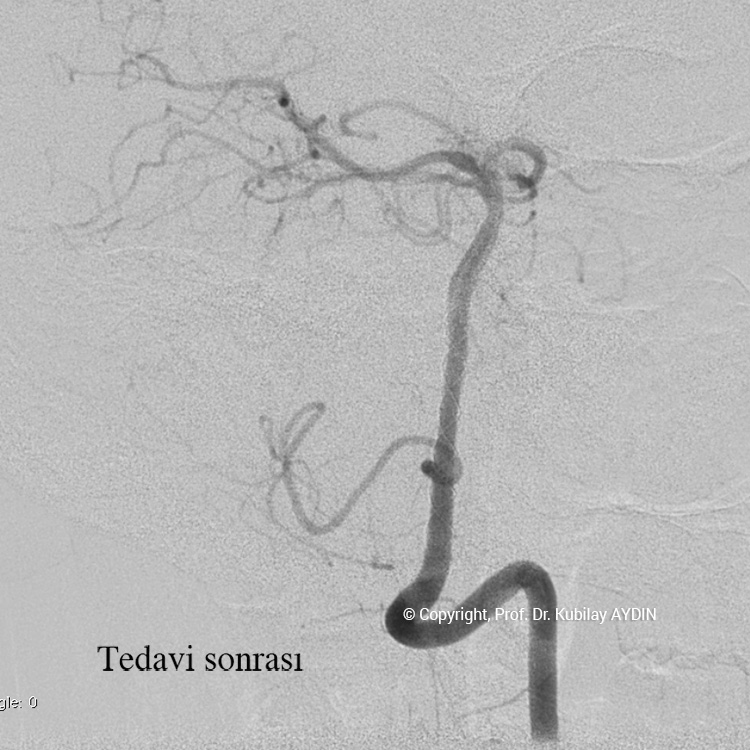

Stent yardımlı koilleme tekniği ile anevrizma tedavisinde, anevrizmanın yerleştiği atardamar içerisine stent açılması için bir kateter yerleştirilir. Eş zamanlı olarak, anevrizma kesesi içerisine koilleme amaçlı farklı bir kateter yerleştilir. Damar içerisine bir stent açıldıktan sonra, anevrizma içerisideki kateterden gönderilen platinden yapılmış çok yumuşak yapıda koillerle anevrizma kesesi doldurulur. Stent, anevrizma içeriside bırakılan koillerin damar içine sarkmasına engel olur. Koilleme işlemine, anevrizma koillerle tamamen doldurulana ve anevrizma içine kan girmeyene kadar devam edilir.